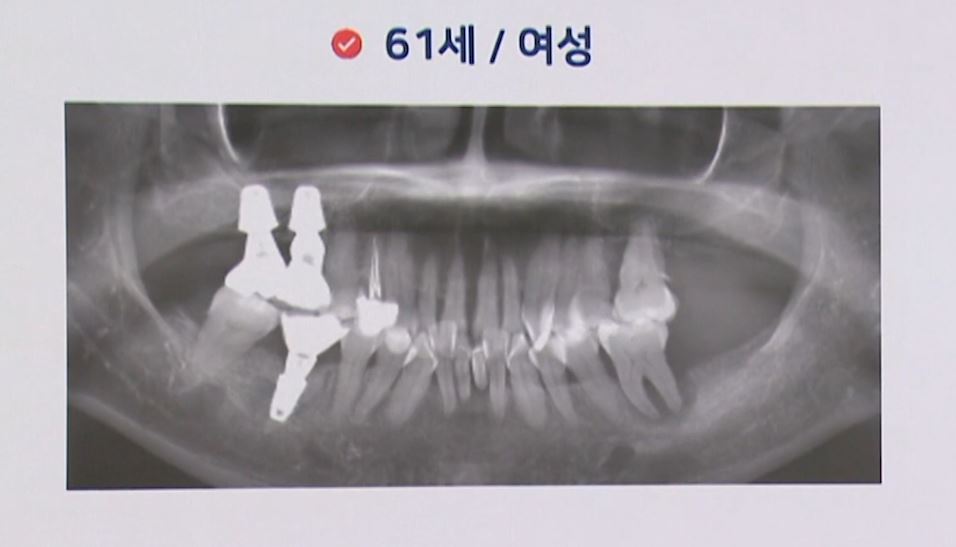

그다음에 여기도 이 상황은 소수 임플란트 상황이거든요, 그 자연치 속에서. 그럼 이 치아를 그럼 내가 약간 움직이고 약간 약한 치아를 빼고 두 개를 씹느냐? 저 치아를 유지하느냐 이런 것들이 과잉 진료와 함께 겹쳐 있지만 유지했을 경우에 이 치아는 약간의 움직임이 있을 수 있다는 거를 환자분이 받아들이셔야 합니다. 그래야 자연치를 잘 보존할 수 있는 것이죠. 이렇게 삐딱하게 누워 있고 좀 흔들린다고 해서 또 다 빼는 거는 치과 회사의 도리가 아닌 것 같습니다. 과잉 진료가 될 수 있는 것이죠. 그러면 이 불편함을 감수하면서 이쪽에 조금 움직일 때 음식이 낄 수 있다. 일단 여기의 양치를 잘하기 위해서 치간 칫솔 같은 걸 사용해서 보조적으로 노력을 해야겠다. 치과에 올 때마다 그쪽을 점검해달라고 또 한 번 더 계속 얘기해야겠다. 이런 과정들이 필요한 것 같습니다.